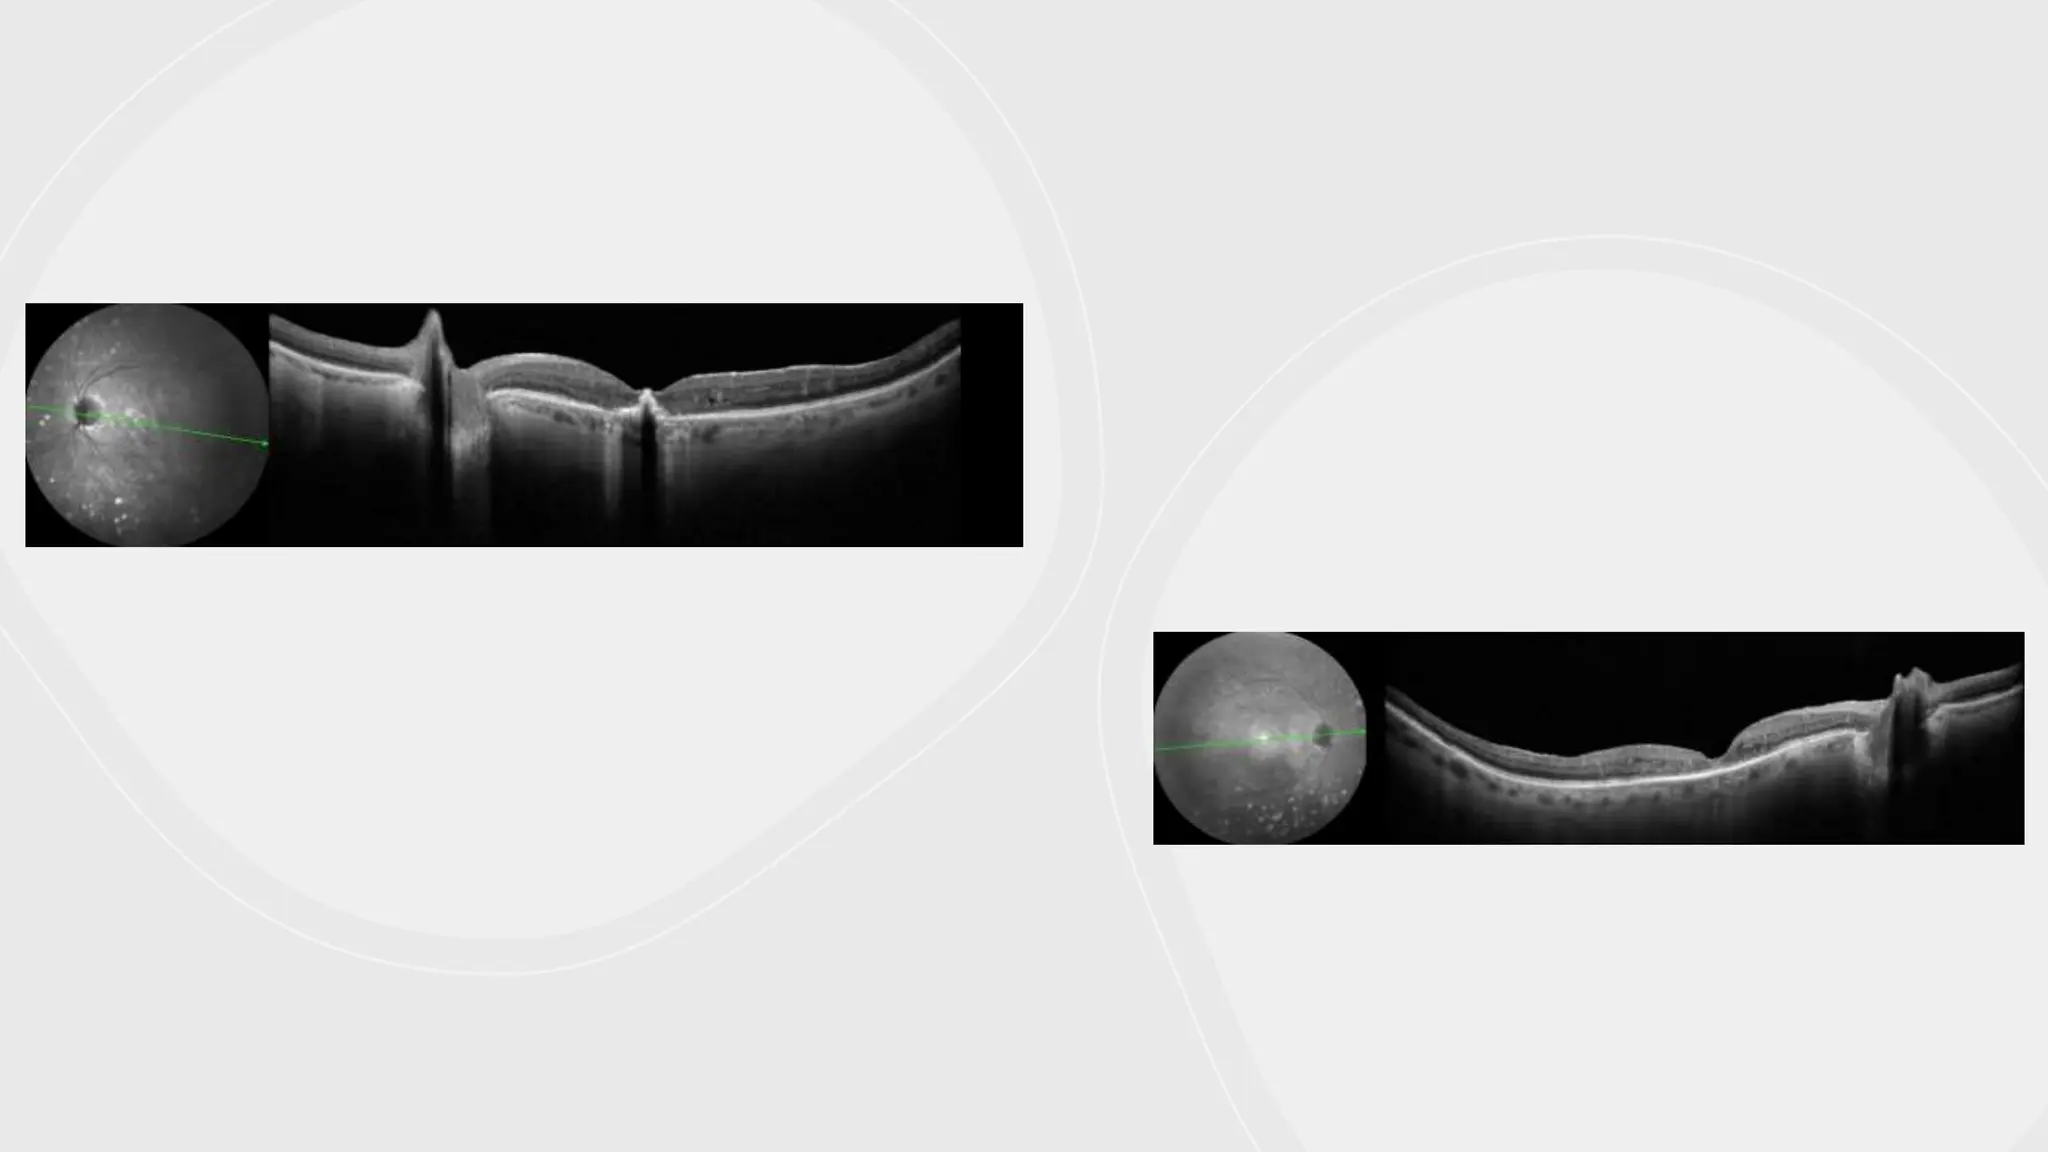

OCT-based classification

• Depending on the morphology of the edema (E)

• E1: diffuse thickening (spongiform) without cysts

• E2: cystic thickening

• E3: detachment of the neuroepithelium

• Depending on the existence of vitreomacular traction (T)

• T0: absence of preretinal hyperreflectivities

• T1: presence of hyperreflective line adhered to the retina without traction

• T2: hyperreflective line with multiple traction points

• T3: hyperreflective line with anteroposterior traction in “gull wings”